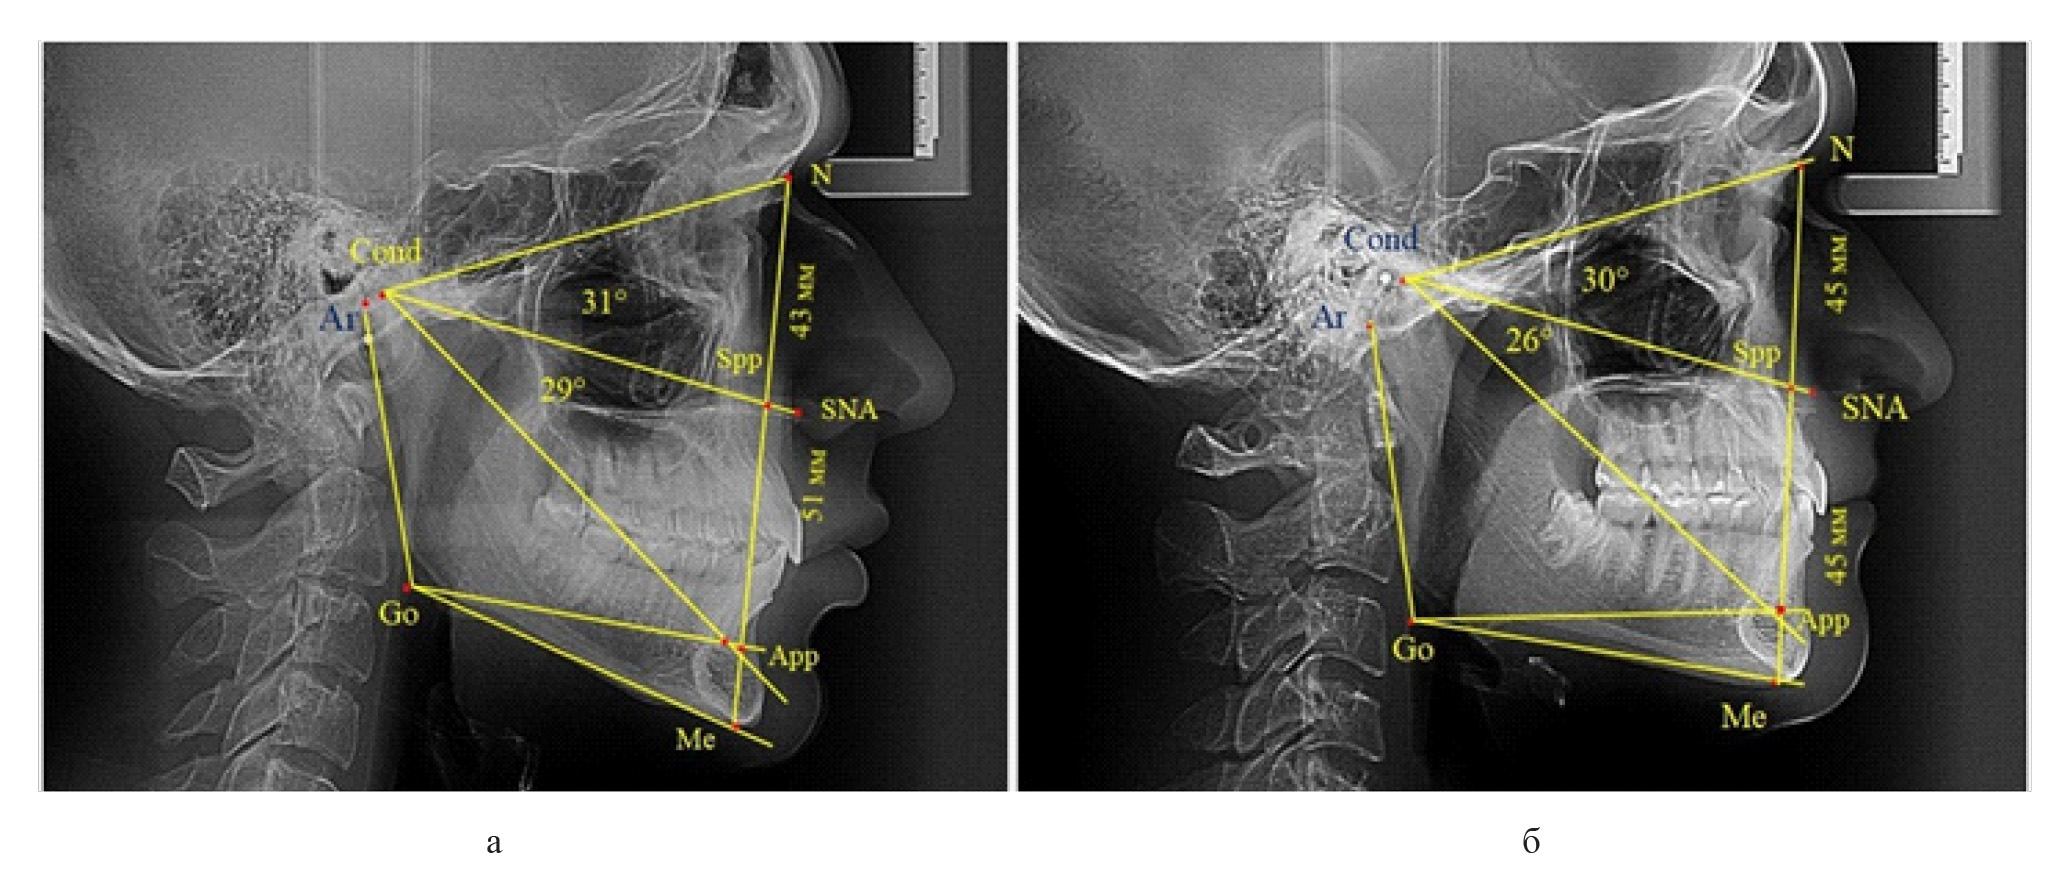

Вертикальная резцовая дизокклюзия (открытый прикус) была проанализирована на 11 телерентгенограммах. При этом отмечались варианты как с оптимальными, так и увеличенными параметрами гнатической части лица при различных типах роста назального отдела, что представлено на рис. 7.

Рис. 7. Сравнительный анализ ТРГ при увеличенных размерах гнатической части с оптимальными (а), укороченными (б) и увеличенными (в) размерами носового отдела лица и вертикальной резцовой дизокклюзией